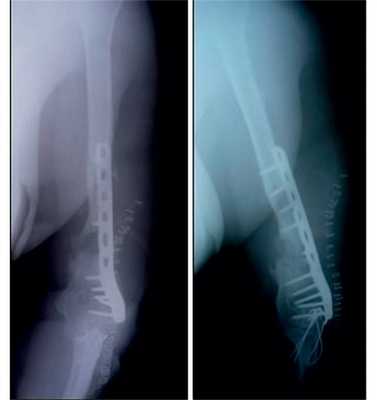

Рис. 11. Пациентка Н. Оперативное лечение: резекция зоны ложного сустава левой плечевой кости, остеосинтез пластиной и винтами. Пластика свободным кровоснабжаемым трансплантатом из внутреннего мыщелка бедренной кости.

Рис. 12. Рентгенограммы пациентки Н. после операции.

Рис. 13. Рентгенограммы пациентки Н. через 8 мес после операции.